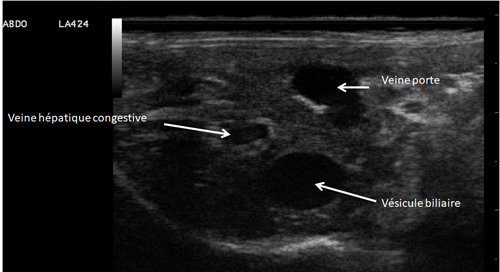

Échographie abdominale

Absence d’ascite et de modification visible à l’échographie du système digestif.

- Echographie : congestion hepatique / H.portale